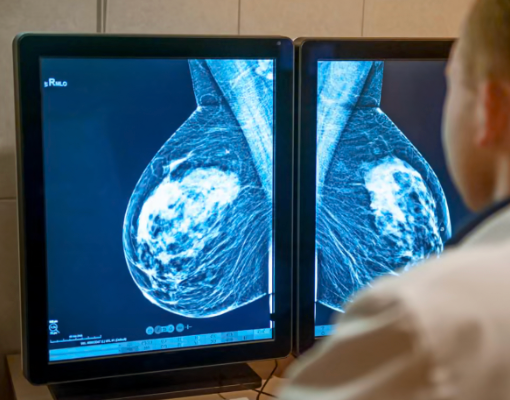

England’s NHS has begun using liquid biopsies. These are blood tests that detect circulating tumor DNA for lung and breast cancer patients. The innovation allows personalized treatment decisions and signals a shift toward precision medicine.

Camizestrant, an oral estrogen-receptor degrader for hormone‑positive, HER2‑negative metastatic breast cancer, delayed the progression by 56% when its use was guided by liquid biopsy monitoring. Aggressive advanced breast cancer further slowed disease progression and postponed chemotherapy needs.